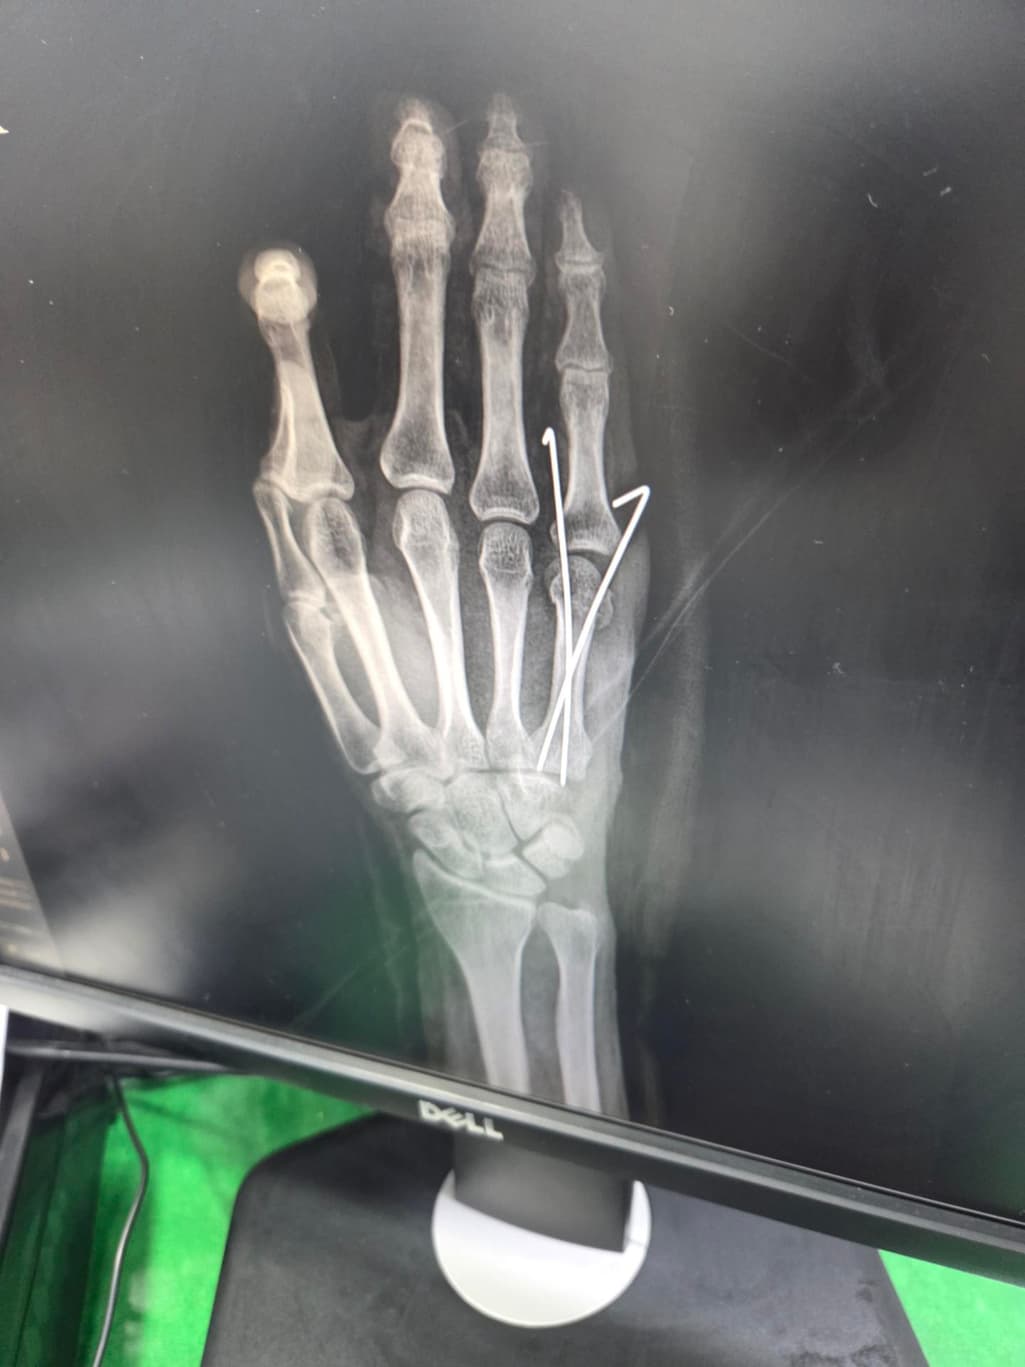

중수골 골절 수술 잘된건지 봐주세요?

수술 직후 사진이고요

두 번째 사진을 보시면 수술한 손가락이 다른 손가락에 비해 뼈가 잘 정렬이 안 된 것 같아서요. 수술적으로 잘못된 부분이 있는지 알려주시면 감사하겠습니다.

엑스레이상으로는 금속 핀을 박은 수술로 보이며 사진상 정확한 상태 확인이 어렵긴 하지만 크게 정렬이 틀어지거나 문제는 없는 것으로 보입니다.

제가 직접적으로 수술의 판단해 드리긴 어렵습니다. 다만 사진상으로는 금속 핀 고정으로 뼈 정렬을 잡은 흔적이 보이며 수술 직후에는 약간의 틀어짐이 있어도 시간이 지나면서 유합과정에서 교정되는 경우가 많습니다.뼈가 완벽히 일직선으로 맞지 않아도 기능 회복에는 큰 지장이 없는 경우도 흔합니다!